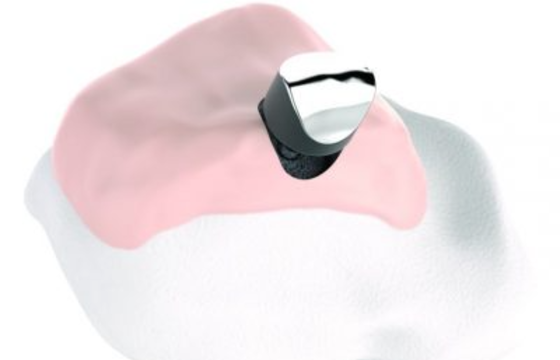

The Episealer Talus is an individualised resurfacing implant intended for use on either the medial or lateral talus. It aims to treat patients suffering from pain and reduced mobility due to focal osteochondral lesions in the talus. The Episealer technology restores the damaged joint surface in order to alleviate pain and quickly enables patients to recover joint mobility.

The Episealer implant comes with an individualised drill guide, Epiguide, and a set of associated tools needed to ensure the best possible outcome. The guide is designed to attach perfectly onto the talus’ surface around the lesion. This provides a stable platform to support you during the drilling process.

The detailed preparation of the lesion site enables a simple and precise insertion of the implant at an exact angle and depth relative to the patient’s joint anatomy. This makes it possible to safe-guard against any part of the implant protruding, a situation which may jeopardise the final result.

The individualised Epiguide’s design is based on the patient’s MR and/or CT images.